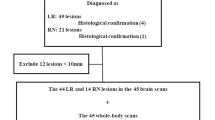

The studied group comprised 420 patients suffering from diagnosed or suspected extra-cranial malignancies referred to our hospital for brain-included whole-body PET/CT assessment and were followed up over a period of 12 months (Fig. 1). Informed consents were obtained from patients prior to conducting the current study, and the study was approved by our local research ethics committee. The clinical evaluation of all patients included full history taking, thorough clinical examination, laboratory evaluation, and other imaging modalities whenever available. Examinations were done and data were obtained using Siemens Bio-graph true point 64 PET/CT scanner. This dedicated system integrates a PET scanner with a multi-slice helical CT scanner permitting the acquisition of co-registered CT and PET images in one session. Inclusion criteria included patients diagnosed/suspected to have extra-cranial malignancy with no history of craniotomy, radiosurgery, or cerebral resection.

The study group comprised of 420 patients suffering from extra-cranial malignancies. Thirty patients had brain lesions with a median age of 58 years (range 45-77, mean ± SD 58.2 ± 9.4 years) and distributed as n = 16 males (53.3%) and n = 14 females (46.7%). Negative radiological findings for brain lesions were initially reported in 390 patients from whom follow-up data could be obtained for 70 patients (the rest of the patients were missed due to losing contact or death). All patients were followed-up over 12 months period for the development of any neurological complaints or positive brain imaging studies.